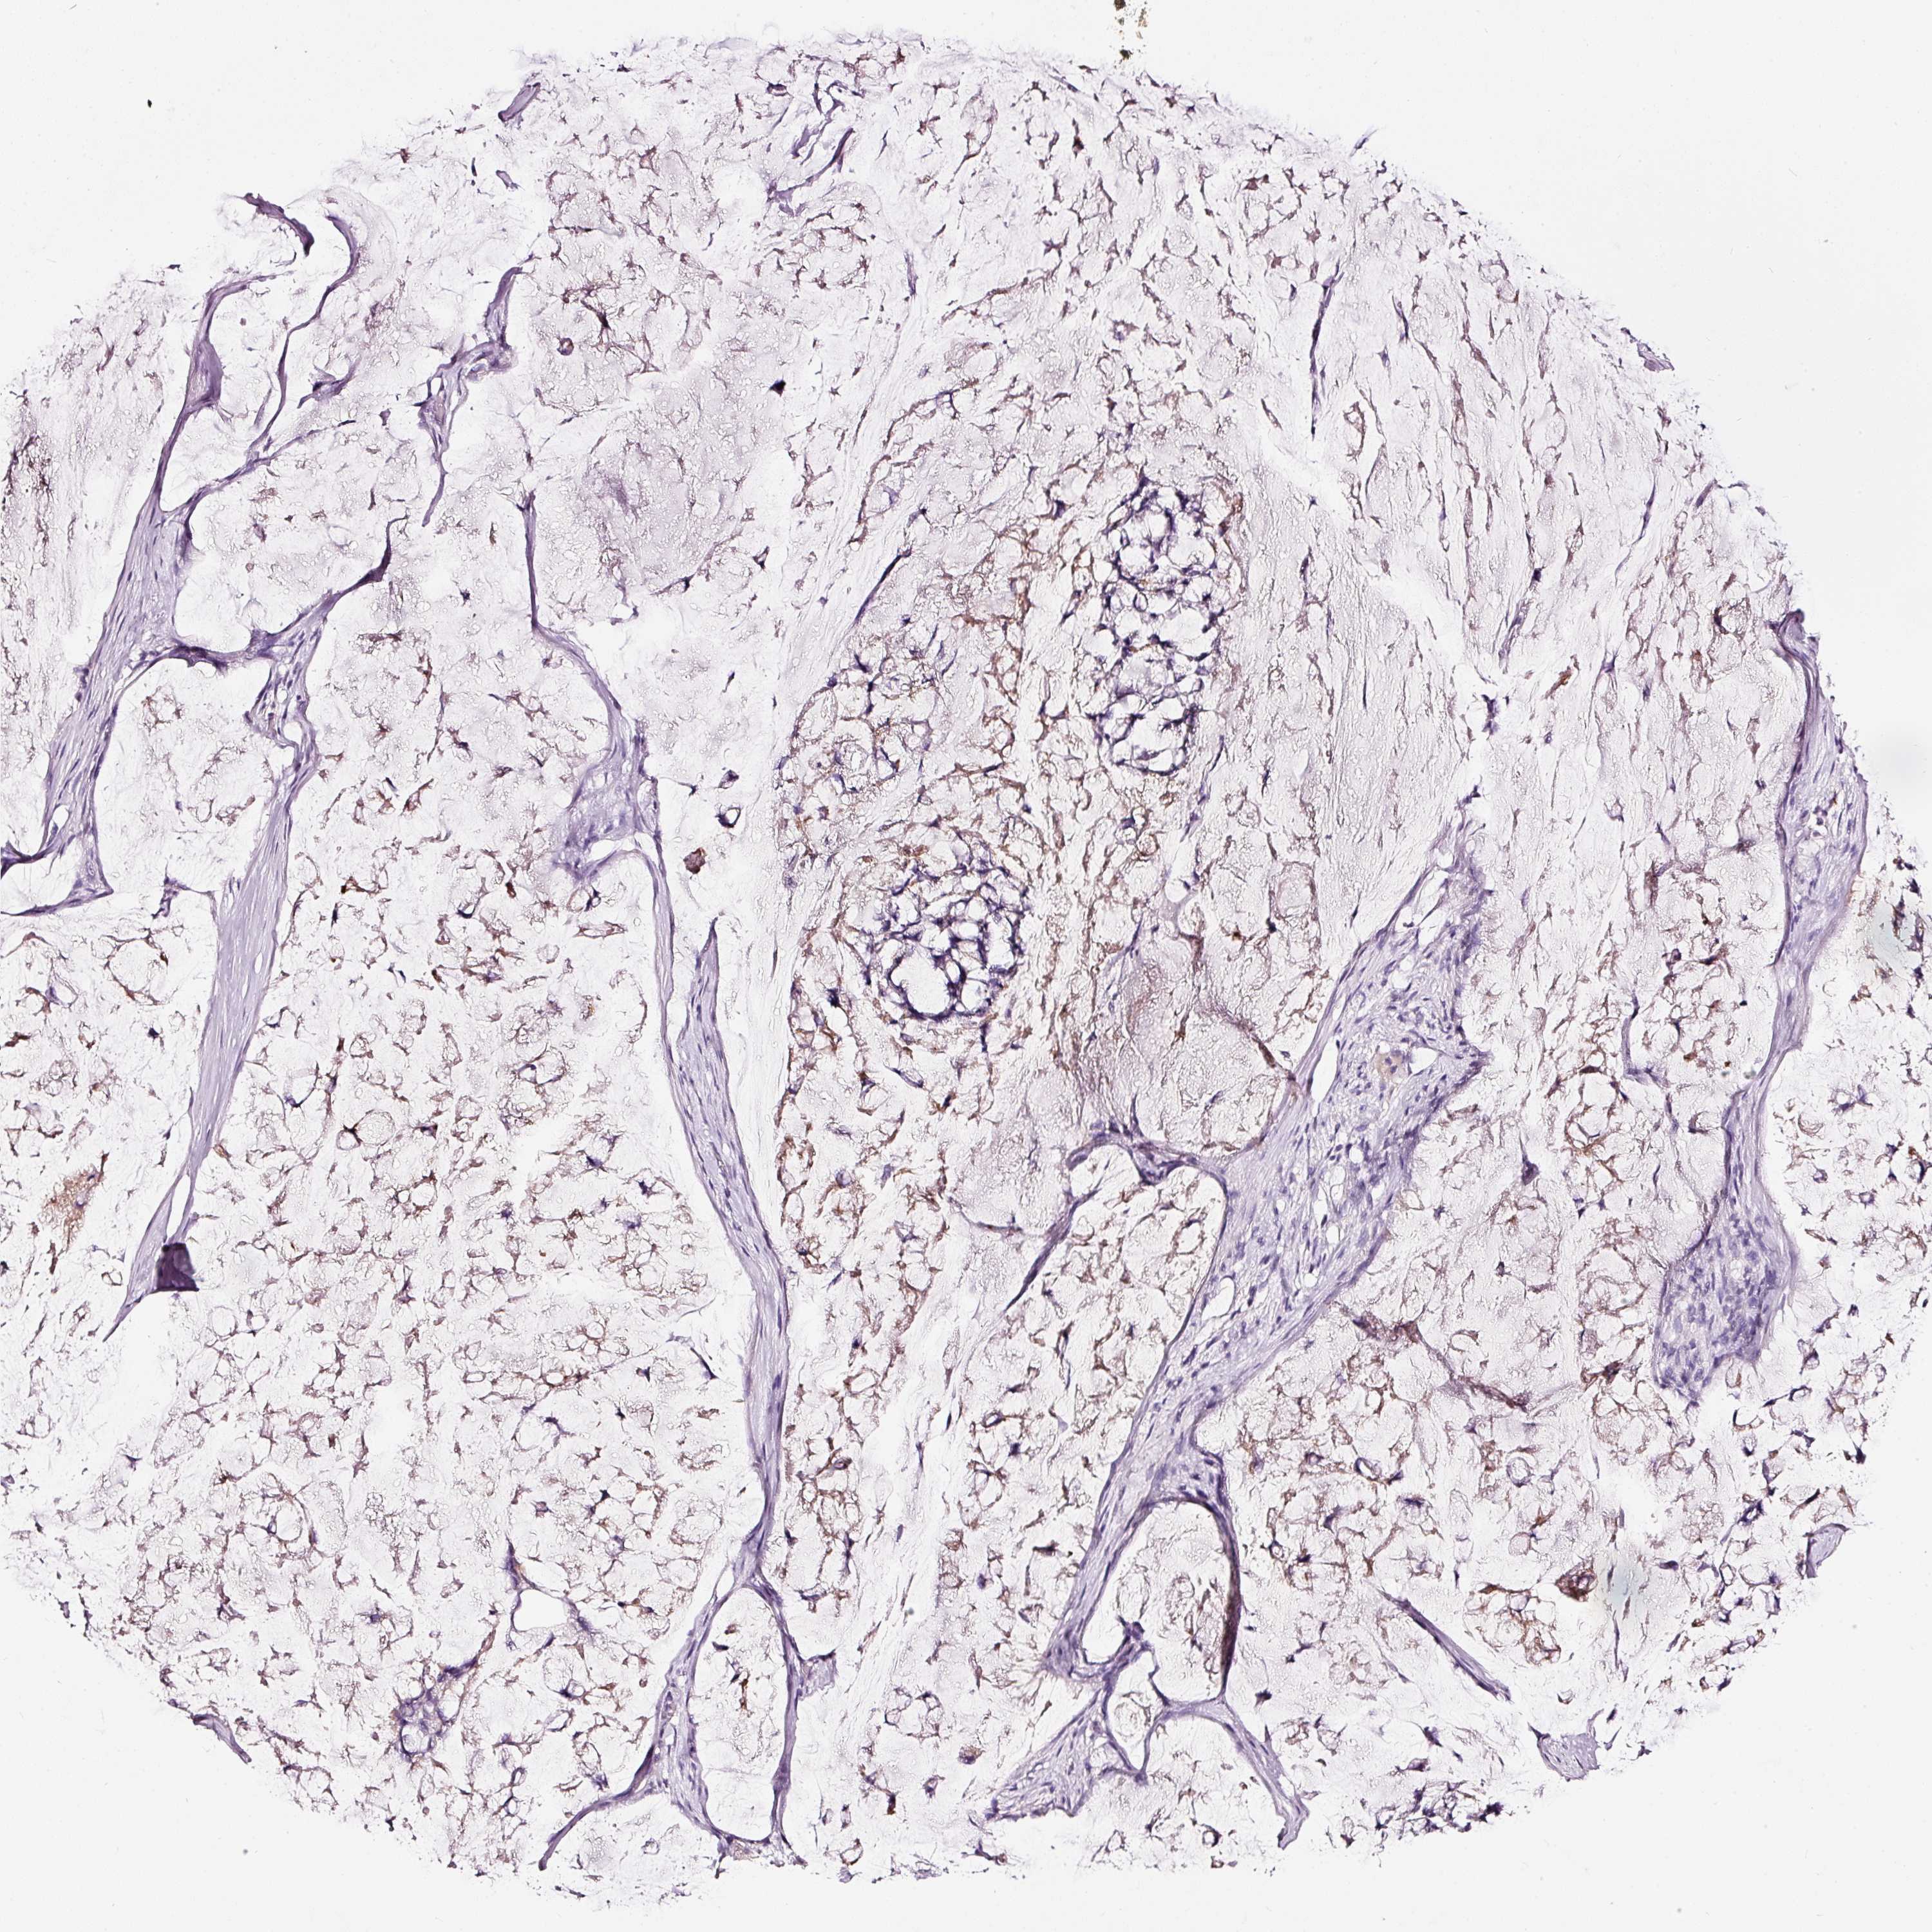

STOMACH CANCER - Protein expressioni

A mouse-over function shows sample information and annotation data. Click on an image to view it in a full screen mode. Samples can be filtered based on level of antibody staining by selecting one or several of the following categories: high, medium, low and not detected. The assay and annotation is described here.

Note that samples used for immunohistochemistry by the Human Protein Atlas do not correspond to samples in the TCGA dataset.

Antibody stainingi

Antibody staining in the annotated cell types in the current human tissue is reported as not detected, low, medium, or high, based on conventional immunohistochemistry profiling in selected tissues. This score is based on the combination of the staining intensity and fraction of stained cells.

Each image is clickable and will lead to virtual microscopy that enables deeper exploration of all samples and also displays staining intensity scores, fraction scores and subcellular localization as well as patient and tissue information for each sample.

Antibody HPA051467

Antibody CAB025133

Staining

High

Medium

Low

Not detected

Intensity

Strong

Moderate

Weak

Negative

Quantity

>75%

75%-25%

<25%

None

Location

Nuclear

Cytoplasmic/membranous

Cytoplasmic/membranous,nuclear

Adenocarcinoma, NOS